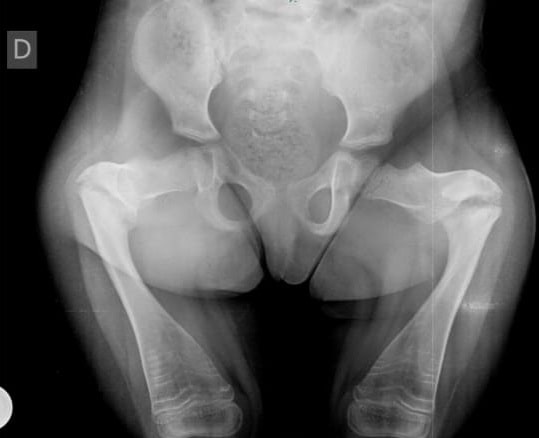

La primera paciente fue una pequeña de 5 años de edad que poseía una osteogénesis imperfecta de grado 3, una enfermedad invalidante que no le permitía caminar.

“Es una patología de origen genético, es decir, es una enfermedad adquirida desde el nacimiento. Consiste en una alteración a nivel de los huesos en los cuales los chicos sufren fracturas a repetición con traumas mínimos, a veces es una caída simple. Tiene que ver con una falla en la clasificación ósea”, manifestó el profesional.

El especialista aclaró que existen diferentes grados. “En un grado bajo, son chicos en apariencia normales, sin embargo, en la expresión más severa de la patología son chicos con baja talla, pequeños con una alteración en el crecimiento y repetidas fracturas”.